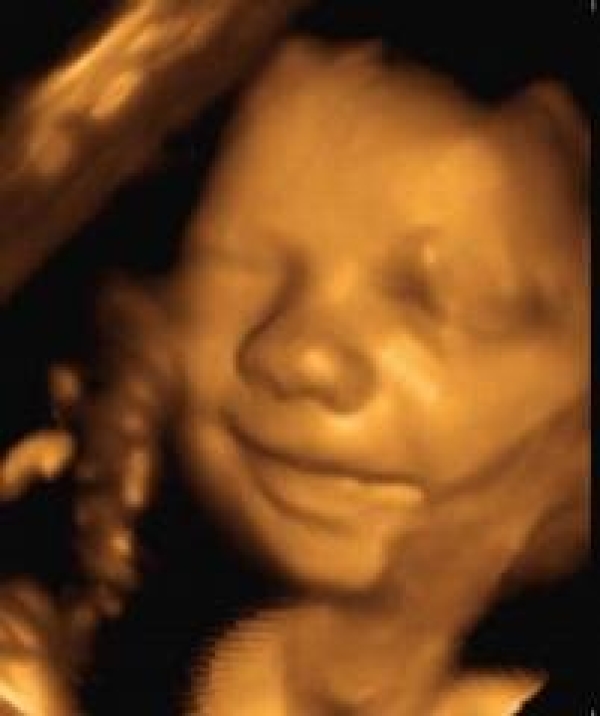

Bu işlemde renkli doppler 3 ile 4 boyutlu görüntüleme teknolojisiyle donatılmış olan ve aynı zamanda yüksek görüntü kalitesine sahip gelişmiş ultrason cihazları kullanılıyor. Hamilelikte üç boyutlu ultrason kaçıncı haftada ve hangi ayda yapılır ilk aylardan itibaren ve ilk haftalarda yapılır. Hamileler için renkli doppleri ne zaman yaptırmak uygundur. Detaylı ultrason 17 ila 23.